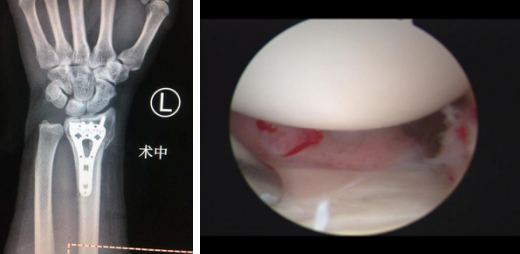

1月2日,齐主任在腕关节镜辅助下为女患者进行了桡骨远端骨折复位内固定术。术中应用牵引架牵引复位左桡骨骨折端,关节镜下复位远端关节面,手腕小切口钢板内固定。

术中